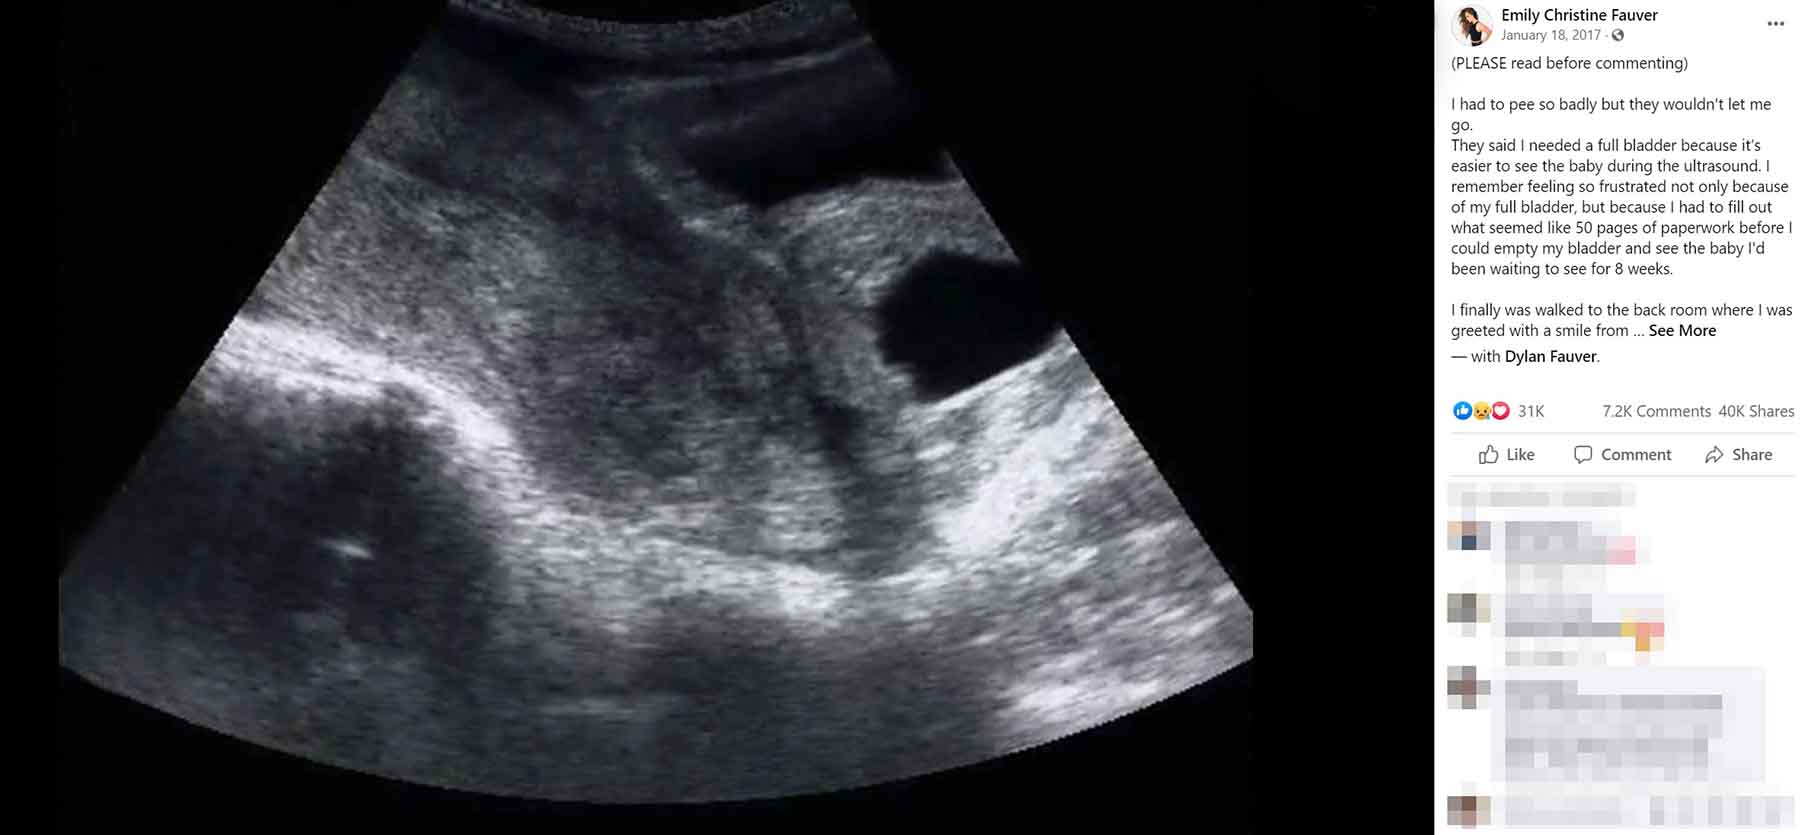

Foto: Instagram/Emily Christine Fauver Foto: Instagram/Emily Christine Fauver Foto: Instagram/Emily Christine Fauver Potresna priča iza jednog ultrazvuka autor: Božica Luković Beba i porodica 30. apr. 2021. 13:37 0 Podeli vest: Emili Kristin Fover bila je sa suprugom na ultrazvuku nakon osam nedelja trudnoće, kad je saznala tužnu vest da je doživela spontani pobačaj. Na svom Fejsbuk profilu podelila je svoju bol i patnju, a onda je i poručila drugim ženama kako nisu same. Podeli vest: Oglas Kao i većina trudnica, Emili Kristin Fover istražila je sve što je mogla pre nego je otišla na pregled kod svoje doktorke u osmoj nedelji trudnoće, piše Miss7 mama.Provela je neko vreme u potrazi za fotografijama drugih ultrazvukova nakon osam nedelja trudnoće, pa je dobro znala šta bi moglo da je čeka na pregledu.Ipak, njen ultrazvuk izgledao je drugačije od onih koje je videla na internetu i znala je da je imala spontani pobačaj i pre nego što joj je doktorka to rekla. Većina fotografija s osmonedeljnog ultrazvuka pokazuju fetus koji je već formiran, ali ona nije videla ništa. Nije mogla da uoči oblik svoje bebe, a tehničar koji je radio ultrazvuk bio je jako tih i mirno je napustio sobu.Emili je fotografiju s ultrazvuka podelila na Fejsbuku, a ona je ubrzo postala viralna."Poslata sam kući kako bi mi telo zacelilo. Osećala sam sve, a ništa se nije pokazivalo. Moja doktorka nije me poslala kući bez upozorenja i bila je u pravu u vezi svega. Ali ono na što me nije upozorila bila je bol koju sam osetila nakon slomljenog srca i patnje", napisala je Emili."Nije mi rekla da će me telo nedeljama nakon toga podsećati na bol koju sam prošla jer će mu toliko dugo trebati da se 'očisti'. Nije mi rekla da ću morati da gledam muža kako plače. Nije mi rekla kako će biti teško da kažem mojoj mami šta se dogodilo. Nije mi rekla kako će moje telo još nedeljama misliti da je i dalje trudno", nastavlja Emili.Ona nije jedina žena koja je ikada bila u potpunosti nepripremljena na fizičke i emocionalne posledice koje dolaze sa spontanim pobačajem, a razlog za to je vrlo jednostavan: o tome se retko govori. Uprkos činjenici da značajan broj trudnoća završi i pre prvog tromesečja, retko kad možemo čuti lične priče žena koje su pretrpele gubitak trudnoće. Ovakve priče obično nisu tema televizijskih emisija ili filmova, iako su hiljade hrabrih žena podelile svoju priču.To je verovatno razlog zašto je Emilin post podeljen preko 33.000 puta, a broj i dalje raste. Ona je svoju priču podelila ne kako bi postala hit na društvenim mrežama već kako bi pomogla mnogim ženama da shvate da nisu same.Na samom kraju svoje priče, napisala je: "To je moja nada za vas... Nadam se da se nećete osećati kao da ste same. Nadam se da ćete sebi dopustiti da plačete. Nadam se da ćete videti svetlo na kraju tunela. Nadam se da, iako je vaša vera stavljena na test, da ćete ipak biti jaki. Nadam se da ćete naći svoj mir. Nadam se da vas neće biti strah da probate ponovno. Nadam se da nećete kriviti sebe. Nadam se da će vas vaši prijatelji zagrliti malo čvršće. Nadam se da ćete nekom drugom podariti nadu. Nadam se da ste svetlost u najmračnijem vremenu... I nadam se da ćete slaviti život tog deteta onoliko koliko ćete slaviti i život sledećeg deteta jer, bez obzira na to koliko kratak život bio, zaslužuje da se slavi - i svi gubici trebalo bi da se oplakuju".https://www.facebook.com/photo.php?fbid=10155019052606579&set=a.98870221578&type=3***Bonus video:https://youtu.be/iBRkAvEy5L8Pratite nas i na društvenim mrežama:FacebookTwitterInstagram Priznanje mame zbog koje joj poručuju da nije zaslužila decu Beba i porodica 0 Mama deteta sa smetnjama: Car:go hteo da mi izbaci ćerku Beba i porodica 0 Najopasnije mesto u kući na kom beba može da spava Beba i porodica 0 spontani pobačaj ultrazvuk Pratite nas na društvenim mrežama: Koje je tvoje mišljenje o ovoj temi? Učestvuj u diskusiji ili pročitaj komentare Budite prvi koji će ostaviti komentar Pošalji komentar Pročitaj komentare (0)